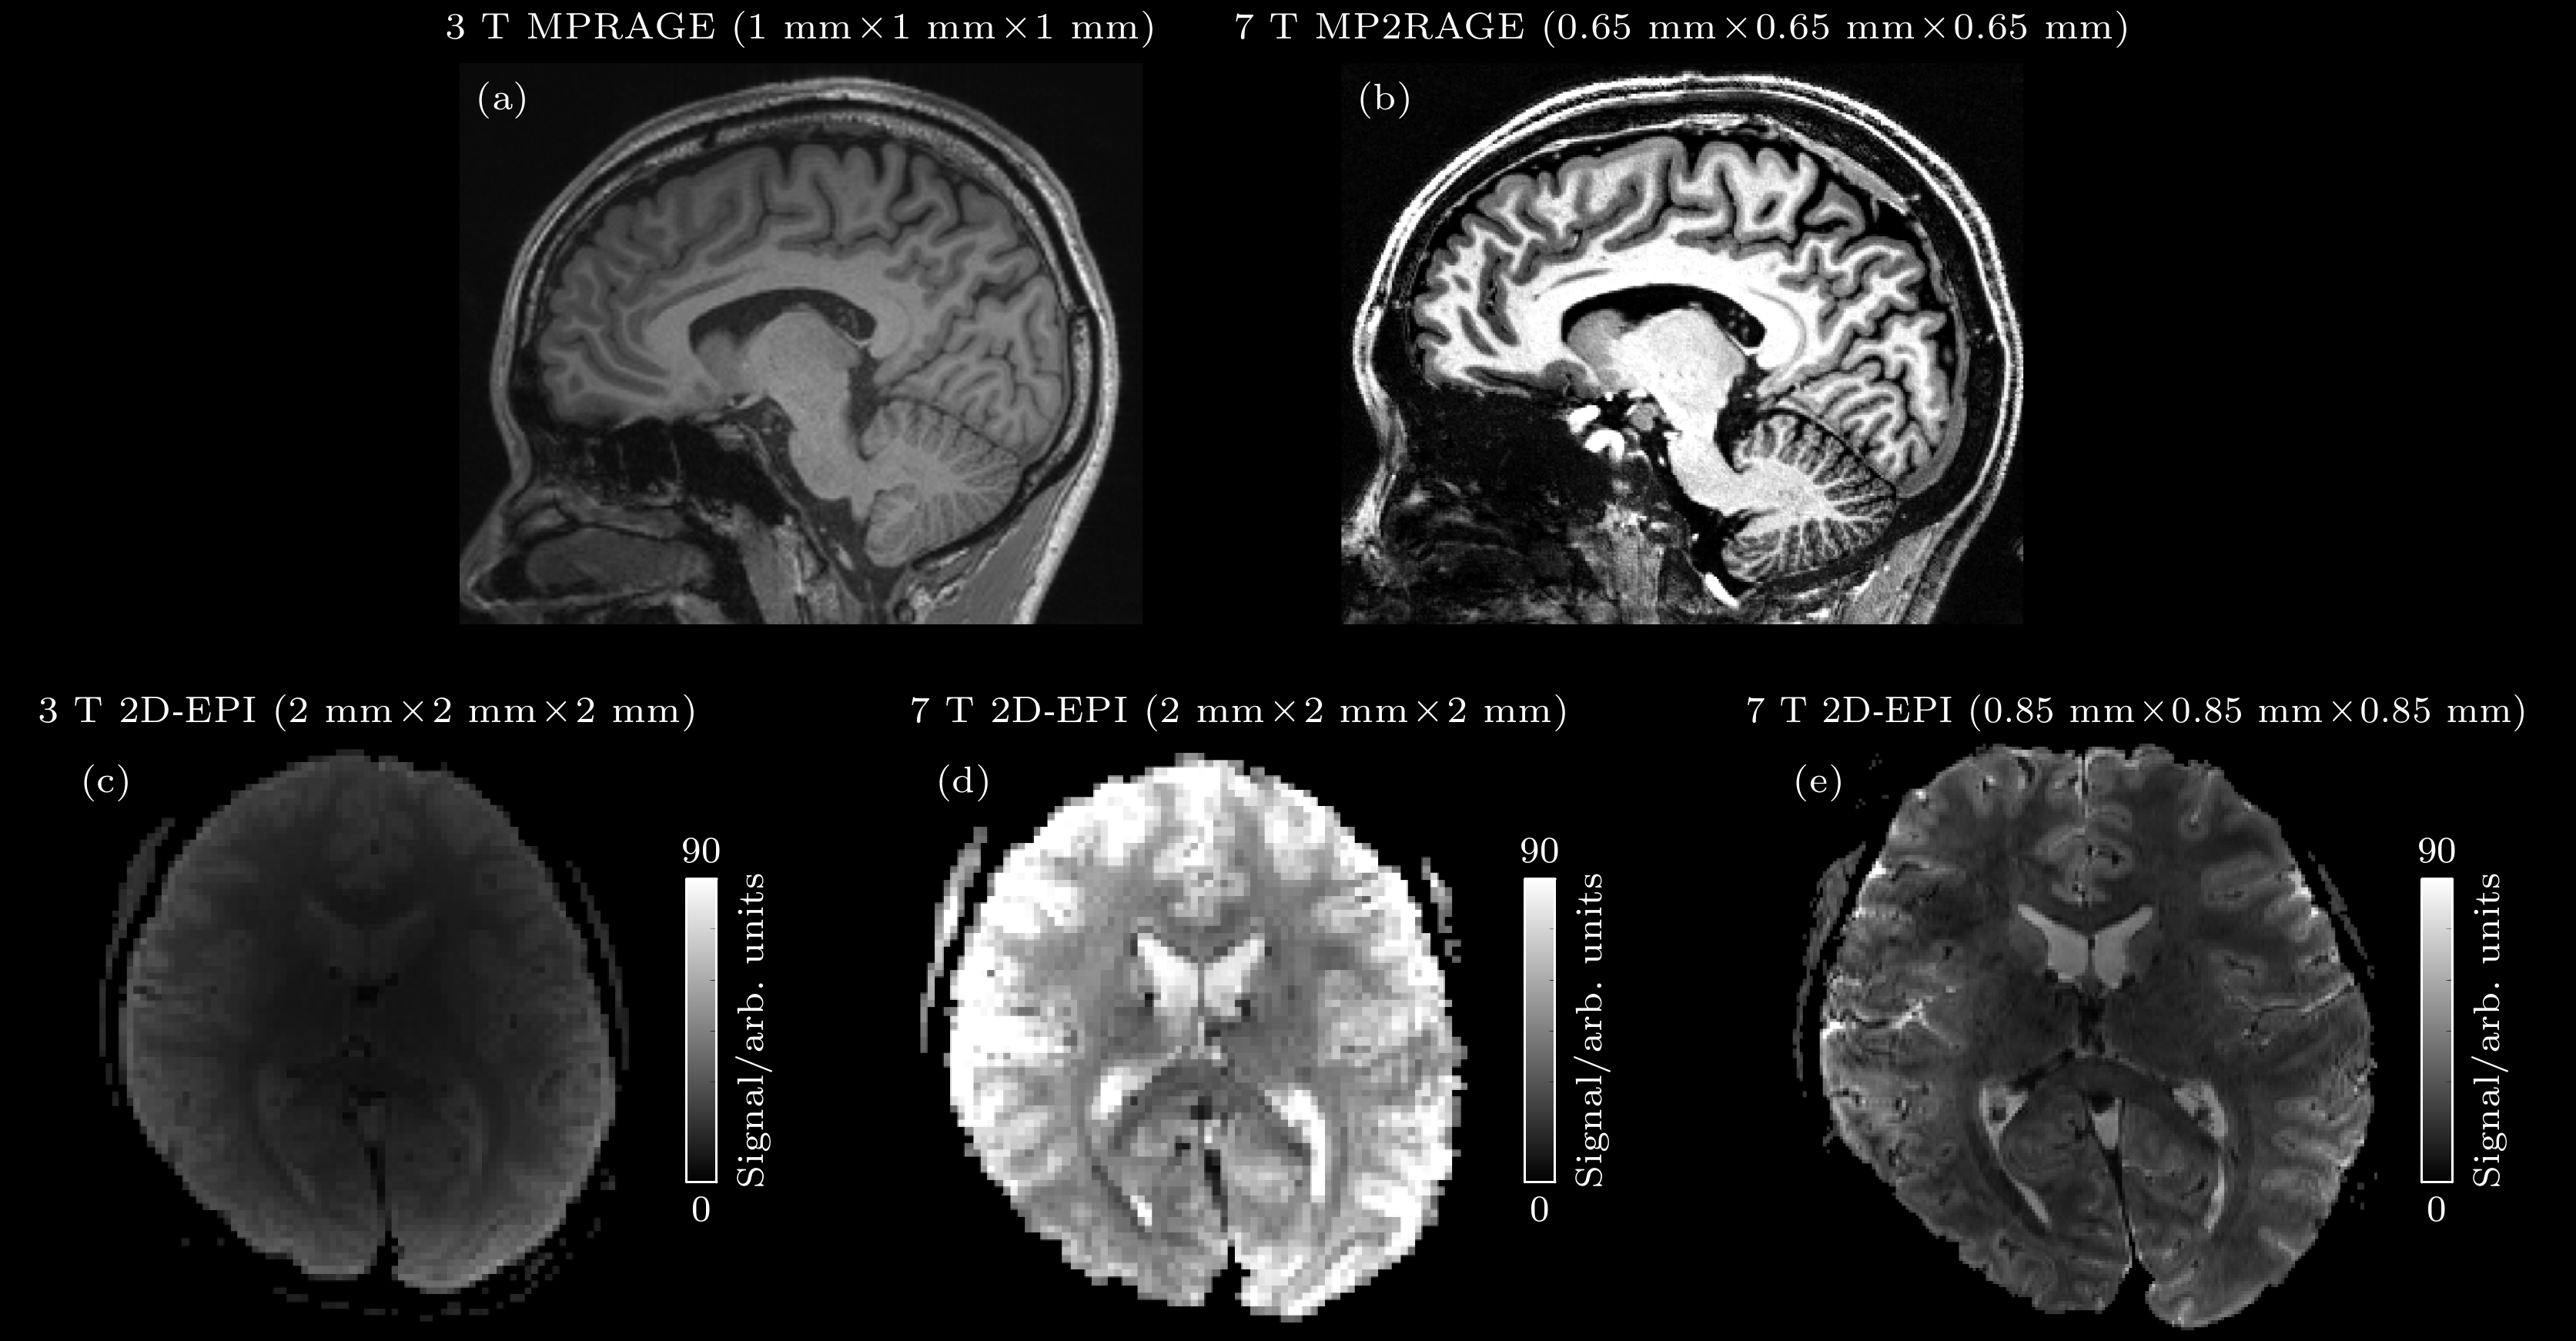

Magnetic resonance imaging (MRI) is one of the most important imaging modalities used in contemporary clinical radiology research and diagnostic practice due to its non-invasive nature, absence of ionizing radiation, high soft tissue contrast, and diverse imaging capabilities. Nevertheless, traditional MRI systems are limited by a relatively low signal-to-noise ratio (SNR), which can be enhanced by increasing the strength of the main magnetic field. Ultra-high field MRI (UHF-MRI) typically refers to MRI systems with a main magnetic field strength of 7 T or higher. The UHF-MRI improves image SNR and extends the boundaries of spatial resolution and detection sensitivity. These advancements not only provide clinicians with richer and more accurate physiological and pathological information but also open new avenues for research on life sciences and cognitive neuroscience. Currently, the UHF-MRI plays a pivotal role in brain functional and metabolic imaging. In the brain function research, the implementation of high-resolution mesoscale functional imaging techniques has enabled the investigation of laminar-specific neuronal activity within cortical layers, including feedforward and feedback neural information processing pathways. In metabolic studies, the application of hydrogen and multi-nuclear spectroscopy and imaging has yielded more accurate metabolic data, thereby holding substantial promise for advancing our understanding of the pathophysiology underlying functional and metabolic diseases. However, the UHF-MRI is also subject to certain limitations, including issues related to radio-frequency (RF) field in homogeneity, elevated specific absorption ratio (SAR), and susceptibility artifacts. In this paper, the historical evolution and theoretical underpinnings of UHF-MRI are reviewed, its principal advantages over low-field MRI is elucidated, and the contemporary research on UHF-MRI applications in human brain function and metabolic imaging research are integrated together. Furthermore, the technical limitations associated with UHF-MRI implementation are critically examined and the potential avenues are proposed for the future research direction.